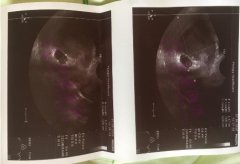

回国后,天天盼着第三代试管筛查结果,由于我爱人的身体差及促排限制用药,我爱人促排出来的卵子只有3枚,其中有2枚培养到了囊胚阶段,总量还是太少了。终于,第一个喜讯在刚刚跨入2020年的时候传来!一枚囊胚通过了NGS第三代试管筛查(如上图)!!!

一锤定影的HCG结果出来了!确认怀孕无疑!!!上图是第三次HCG的结果,第一次HCG的结果只有186!第三次测量的时候,HCG翻倍已经翻得很好了!谢天谢地!感谢天德海外&安娜喜孕!感谢美丽善良的DY妈妈薇拉!